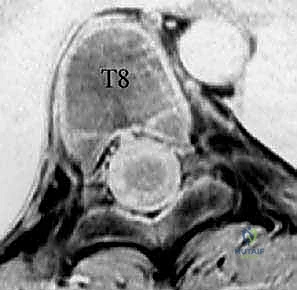

* التصوير بالرنين المغناطيسي (MRI): لاستبعاد أي تشوهات في الحبل الشوكي (مثل تكهف النخاع أو الحبل الشوكي المربوط).

* الأشعة المقطعية (CT Scan): في الحالات المعقدة، لبناء نموذج ثلاثي الأبعاد للفقرات يساعد في تخطيط مسار الأوتاد الفقرية بدقة متناهية.